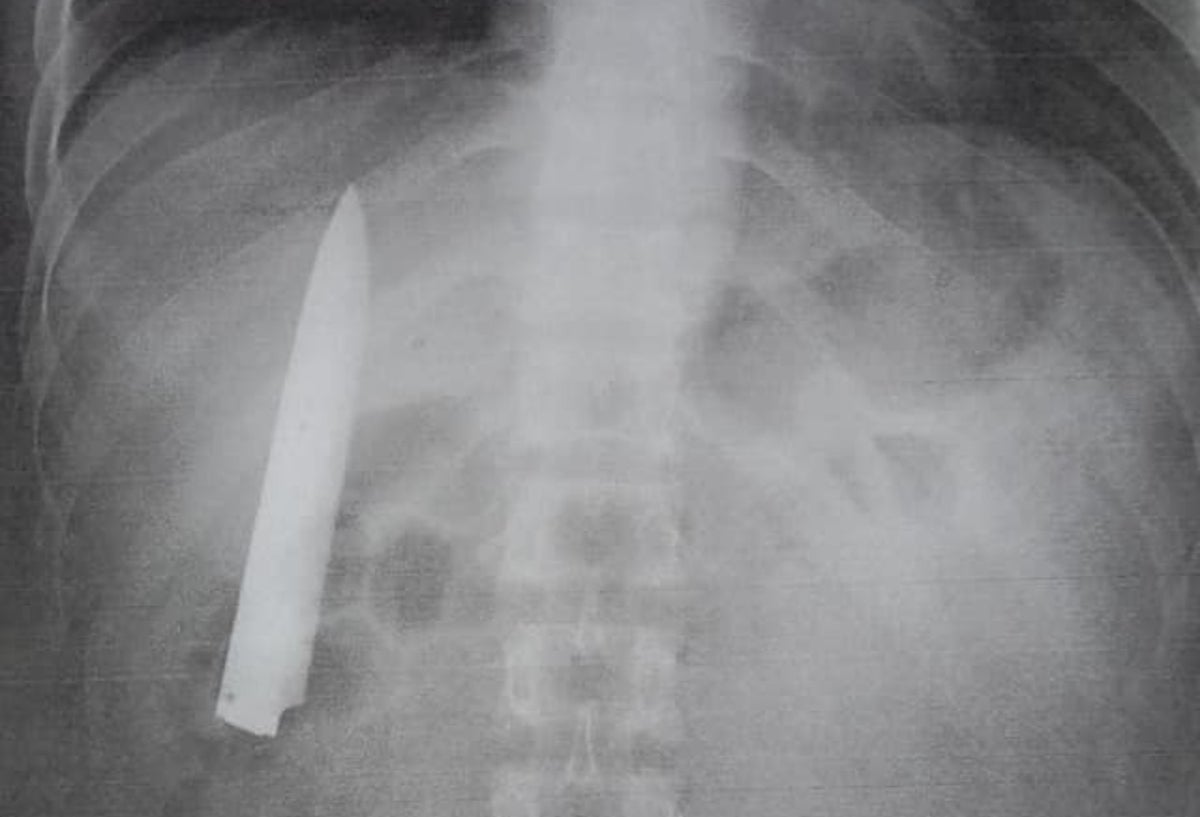

Hombre lleva 14 meses con la hoja de un cuchillo en su torso

Gracias a unos exámenes para el trabajo, el hombre se dio cuenta de lo que tenía en el interior de su cuerpo.

Hoja de cuchillo en un cuerpo

Crédito: Facebook: Panay News

Un hombre sobrevivió catorce meses con una hoja de cuchillo dentro de su torso. El insólito caso se presentó en la ciudad de Kidapawan, Filipinas.

Kent Ryan Tomao fue víctima en enero de 2020 de una brutal agresión por parte de unos adolescentes que lo apuñalaron. El personal médico que lo atendió en aquella ocasión, en una evidente irresponsabilidad, no le realizó exámenes para verificar la profundidad de la herida, sino que procedió a suturarla.

Hace unos días, Tomao aplicó a un empleo en ese país, por lo que le solicitaron unos requisitos en los que incluía una prueba de rayos X. De esta forma, el hombre se dio cuenta que llevaba catorce meses con la hoja de un cuchillo en el interior de su cuerpo.

Al ser preguntado por medios locales, como ABS-CBN, si nunca notó la presencia de un objeto extraño en su torso, Tomao aseguró que cuando el clima era frio sentía algo de dolor en el pecho, pero no le prestaba atención.

Asimismo, explicó que el cuchillo debe ser extraído lo más pronto posible, ya que se encuentra muy cerca de los pulmones y corre riesgo su vida.

El hombre, de 25 años de edad, no tomará acciones legales contra el hospital que lo atendió al sufrir el ataque de los adolescentes; sin embargo, señaló que asistirá a ese lugar para que le quiten el peligroso objeto de su cuerpo.